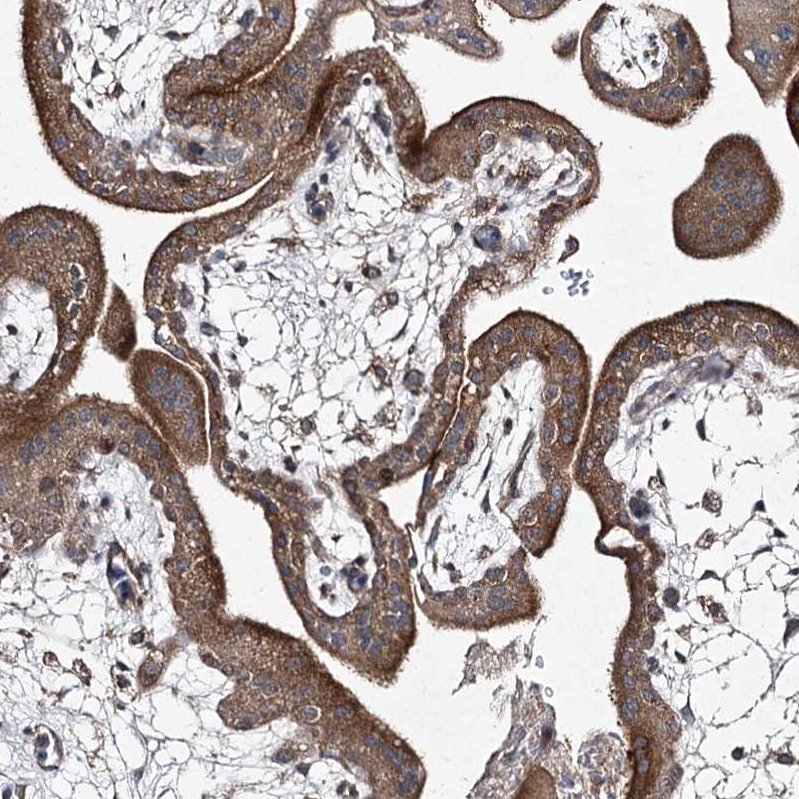

Immunohistochemical staining of human kidney shows moderate cytoplasmic positivity in cells in tubules.